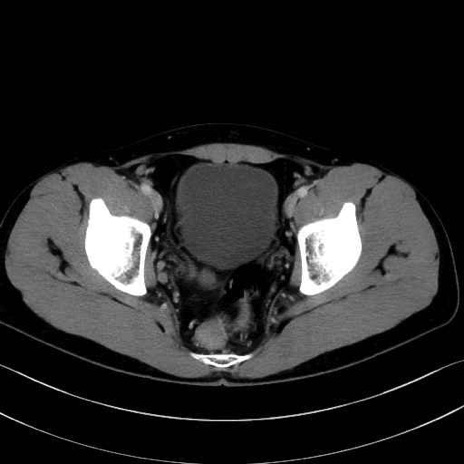

3. 殿部の筋肉(表層・中層・深層)

大殿筋 (Gluteus maximus)

中殿筋 (Gluteus medius)

小殿筋 (Gluteus minimus)

大腿筋膜張筋 (Tensor fasciae latae)